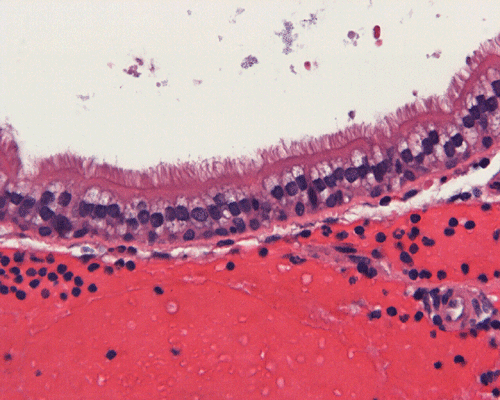

Clinical informationThe patient was a 45 year-old man who presented with staring episode that is reminiscent of a seizure. MRI examination disclosed a cystic sellar mass that deflected his optic nerve. There was no clear visual loss.

Com403-1-MRI1.gif (175407 bytes) Com403-1-2.gif (140093 bytes) Com403-1-4.gif (125178 bytes) Com403-1-1.gif (139689 bytes) Com403-1-3.gif (145349 bytes)

What is your diagnosis? Discussion